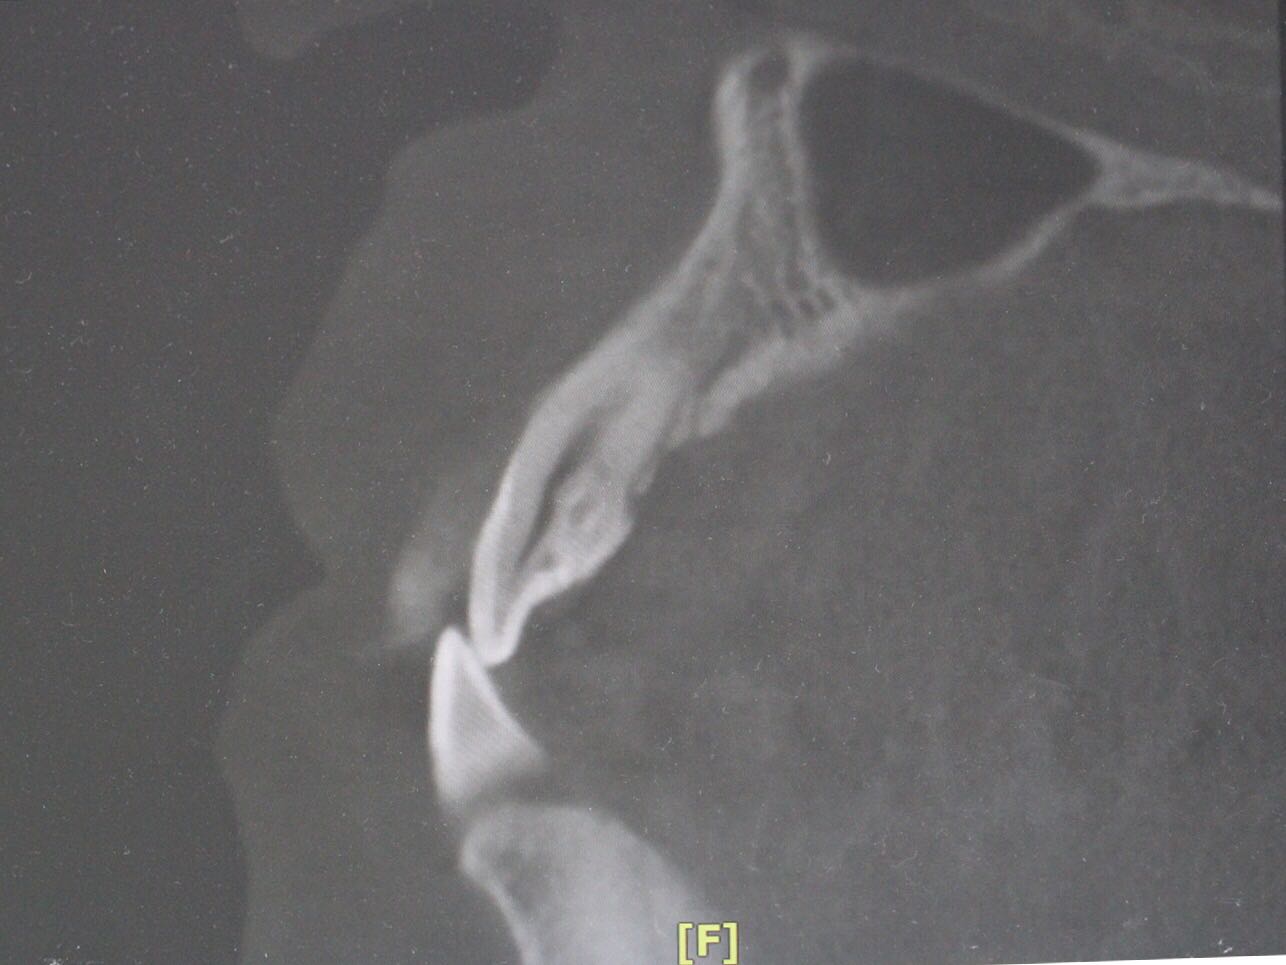

检查:12牙未见明显龋坏,探(-),冷(-),叩(++),无明显松动,牙髓电活力测试无反应,唇侧牙槽粘膜处未见窦道。 X线片:12牙根尖周暗影?

诊断:12牙牙髓坏死? 治疗方案: 1、12牙根管治疗+充填治疗+冠修复 2、12牙择期治疗 3、12牙显微根尖外科手术 4、12牙拔除 5、12牙观察 治疗计划:与患者交流沟通并详细介绍每种治疗方案、费用、时间、预后等,由于患牙根尖病变范围较大,预后欠佳。患者知情、同意并选择方案2,签署知情同意书。 12牙涡轮机开髓,探查根管口,10#,15#K锉疏通根管,根长测量仪测量根管长度,12牙22.5mm,髓腔和根管内放置根管润滑剂,S3扩锉至2506,拍片试尖,X线片示主尖合适。次氯酸啊冲洗根管,P5荡洗,纸尖干燥根管,置氢氧化钙,Caviton暂封。

处置:12牙去暂封,去棉球,根管及髓腔消毒并再次测量并确定根管长度,干燥后,显微镜下使用根尖孔生物材料加大锥度牙胶尖及热牙胶行根尖屏障封闭成形及根管充填,再拍X线片检查根充效果,X线片示根充良好,窝洞消毒,暂封。 医嘱:不适随诊,勿用患牙进食